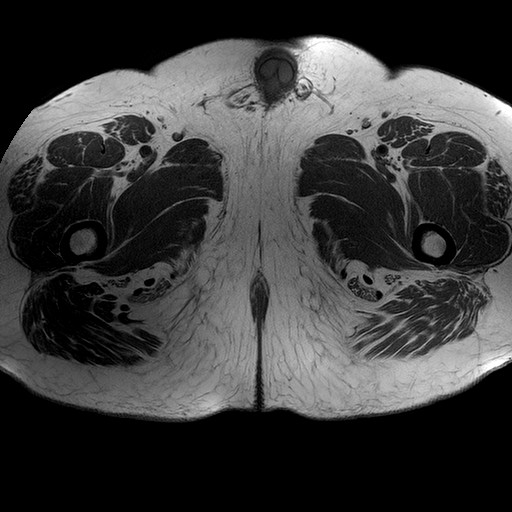

Esami: RMN BACINO

T1W_TSE

Evidenti e simmetriche alterazioni osteofitosiche in regione coxo femorale con riduzione delle rime articolari. Degenerazione completa del cercine glenoideo. Non attuali segni di versamento articolare. Non segni di edema osseo che escludono attuale algodistrofia od osteonecrosi. Lieve e simmetrica riduzione del trofismo della muscolatura glutea.